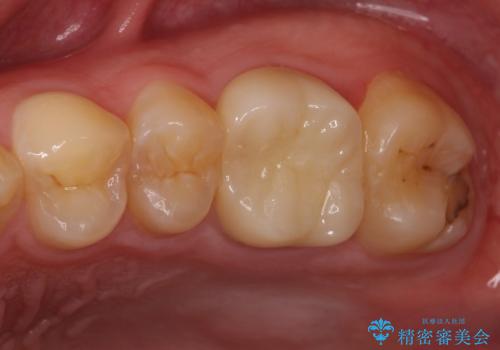

根管治療を実施した後、フルジルコニアクラウンに補綴することとしました。

前医での処置後、治療前には気にならなかった痛み続いていたようですが、当院での処置後は痛みが徐々に引いていき、治療から半年が経過した時点では全く違和感も感じなくなりました。

根管治療後のクラウンも、まるでもとの自分の歯のように自然な仕上がりとなり、患者様には大変満足していただけました。